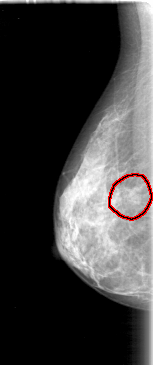

FILE: D_4085_1.RIGHT_CC.OVERLAY

TOTAL_ABNORMALITIES 1

ABNORMALITY 1

LESION_TYPE MASS SHAPE OVAL MARGINS OBSCURED

ASSESSMENT 0

SUBTLETY 3

PATHOLOGY BENIGN

TOTAL_OUTLINES 1

BOUNDARY

RIGHT_CC LINES 4681 PIXELS_PER_LINE 2191 BITS_PER_PIXEL 12 RESOLUTION 43.5 OVERLAY